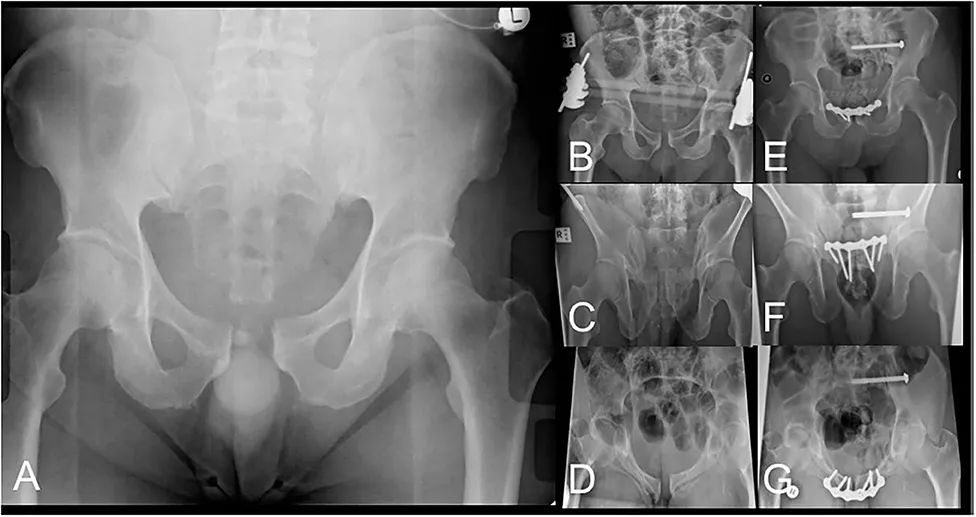

图 6骨盆损伤的AP骨盆X光片(A)分类为左侧APC2。LPEF应用后的AP (B)、出口(C)和入口(D)射线照片显示骨盆对线得到改善,等待最终的手术治疗。AP (E)、出口(F)和入口(G)的X光片在去除LPEF后最终固定后。